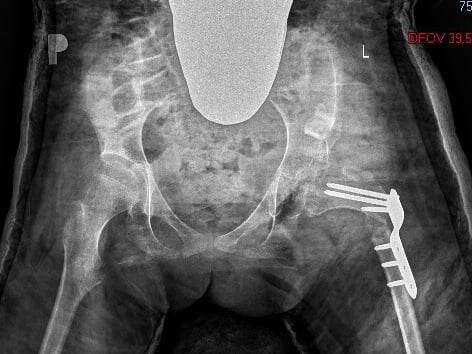

Do blogu przygnały mnie zdjęcia i tu Was zaskoczę – rentgenowskie – na których widać różnicę w obrazie bioder Julci przed i po operacji.

Zastanawiałam się jakiś czas czy to dobry pomysł je zamieszczać ale wiem że są ich ciekawi rodzicie z którymi mam kontakt z wieloma a którzy są przed, w trakcie lub krótko po takiej samej operacji swoich dzieci.

Ja przed operacją też przemierzałam bezkresne przestrzenie internetu szukając podobnego porównania i niestety nie udało mi się trafić na choćby podobny przypadek.

Wypełniam więc lukę i mam nadzieję że zdjęcia pomogą nieco szukającym informacji o operacji bioder spastycznych rodzicom.

Julka miała dodatkowo nacinaną miednicę i uzupełnioną kością pobraną ze skróconej kości udowej.

Jak widać na drugim zdjęciu biodro jest wzmocnione blachami przymocowanymi na śruby, ten „zestaw” będzie do wyjęcia za rok od operacji czyli w maju przyszłego roku.